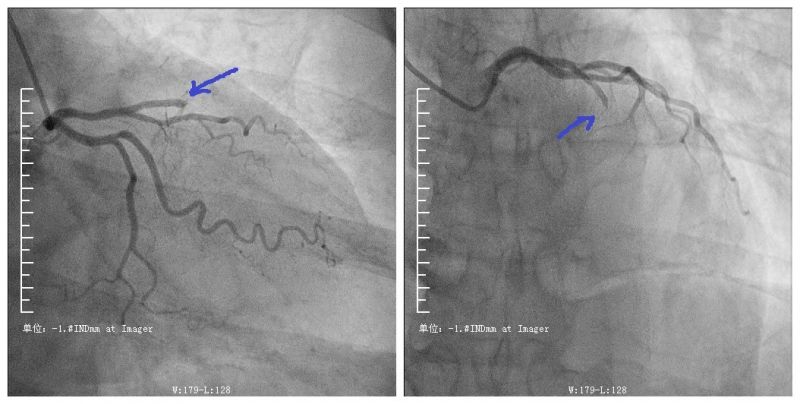

上图所示为堵塞的冠状动脉

今年63岁的芝罘区居民老李,平日里自觉身体良好。前两天的一个下午他突然感到胸口闷痛,时好时坏,当时他也没当回事。第二天再次出现胸闷、胸痛等症状,疼痛的程度比昨日明显加重,他随即赶往烟台山医院南院区就诊。在这里,老李接受了心电图检查,医生考虑诊断为“冠心病 急性心肌梗死”。医生通过急诊手术为老李开通闭塞的心血管,老李转危为安,此前胸闷、胸痛的症状也随之消失。

急性心肌梗死是冠心病的一个类型,是由于给心脏供血的冠状动脉急性堵塞所致。如果把人体比作一辆车,心脏是“发动机”,那么心脏的冠状动脉就是“发动机”的“供油管”,若“供油管”堵塞,“发动机”就会运行不畅。